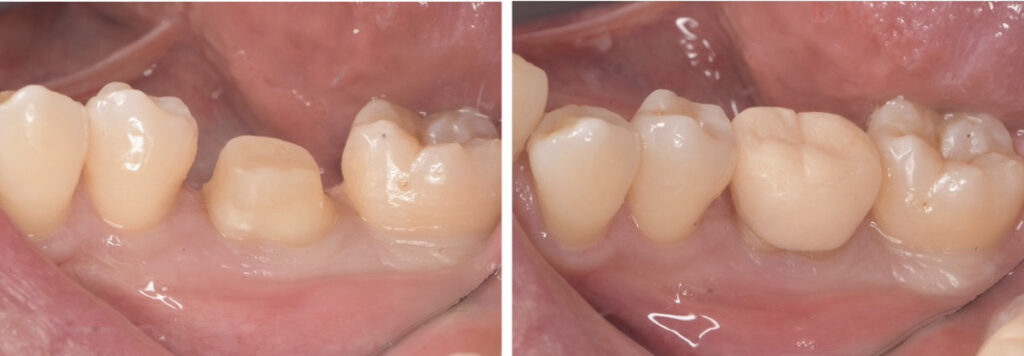

• ファイバーコア(土台)を立てる

• 仮歯の装着

この後、最終的な被せ物(今回はジルコニアクラウン)を被せて治療は終了です。